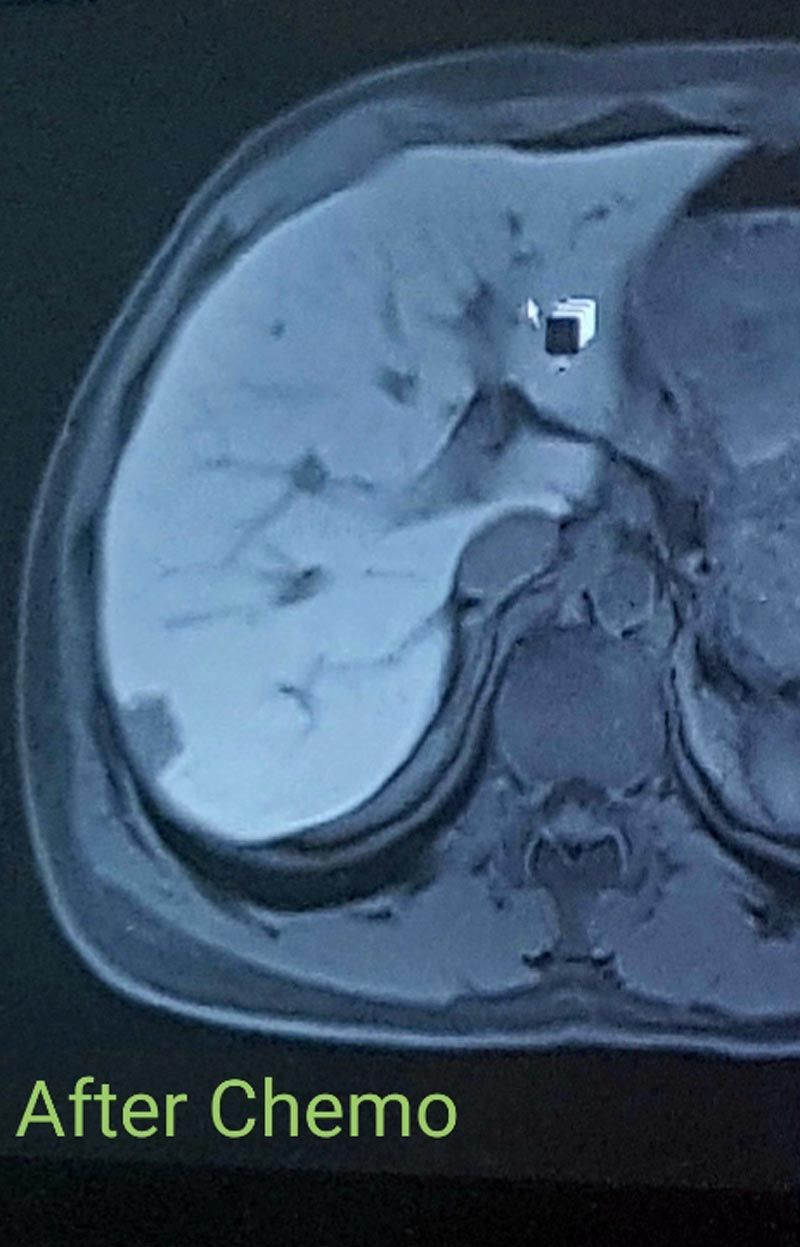

“Chemo completely wiped me out. But, at the end of the three months, I was rescanned and it had done its job."

“The tumors in my liver had reduced enough for doctors to be able to operate."

Initially, it seemed that the tumors in his liver were inoperable, and doctors explained that he would need to undergo chemotherapy to see if they shrank – in which case, surgery could be possible.

In January, he started five rounds of chemotherapy over three months, meaning he had to give up work while Carlie progressed with the pregnancy, doing her best to keep calm and not get stressed.